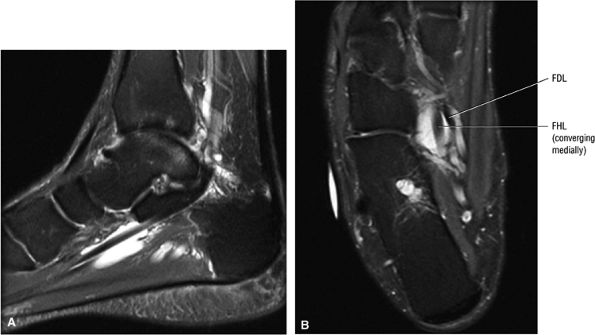

FIGURE 5.26 ● Coronal anatomy of the ankle and foot. (A) The calcaneofibular ligament (CFL) is identified by finding its origin at the inferior tip of the lateral malleolus. The posterior inferomedial course of the CFL is followed on three or four consecutive coronal images moving posteriorly through the ankle, to its insertion on the posterolateral calcaneus. Optimal evaluation of the CFL involves examining its full course on successive images in both the coronal and sagittal plane for tears, sprain, or scarring. (B) The medial cord of the plantar aponeurosis is normally slightly thicker than the lateral cord, and this mild asymmetry in thickness should not be misinterpreted as plantar aponeurosis scarring or plantar fasciitis. On successive coronal images, the course of the plantar aponeurosis should be followed back to its insertion on the inferior calcaneus and evaluated for the presence of thickening, decreased signal suggestive of scarring, increased signal indicative of plantar fasciitis, and tears. (C) Coronal images are optimal for viewing the lateral process of the talus, which is a frequent site of fractures that are occult on plain films. Fractures of the lateral process of the talus are most common in patients with snowboarding injuries. (D) The talar dome and tibial plafond are optimally visualized on coronal images. They are assessed for the presence of subchondral edema and cystic change with overlying chondral abnormalities. Close attention should be directed to the extreme anterior and posterior margins of the cartilage-bearing articular surfaces of the talar dome and tibial plafond to avoid overlooking osteochondral lesions at these locations. (E) The origin of the anterior talofibular ligament (ATFL) is found at the anterior distal tip of the lateral malleolus, and the ATFL is followed anteriorly on two or three successive coronal images to its insertion at the anterior lateral margin of the talus. (F) The deltoid ligament is optimally visualized in the coronal and axial planes. Tears of the deltoid manifest as loss of fiber striation or diffuse amorphous hyperintensity in the ligament on fluid-weighted sequences. Partial tears are more common than complete tears. (G) Focal fatty atrophy and denervation of the plantar flexor muscles of the foot (abductor digiti minimi, flexor digitorum brevis, and abductor hallucis) may indicate neuropathy involving the tibial nerve or its branches. (H) At the level of the anterior aspect of the talus and calcaneus, the peroneal tendons and flexor tendons turn from their cranial—caudal course to travel an anterior-to-posterior course along the plantar aspect of the foot. The distal portions of the tendons should be examined along the plantar aspect of the foot on successive coronal images for evidence of tendinosis and tears. (I) The base of the fifth metatarsal is a common location for fractures and is often visualized within the FOV on ankle MR exams. (J) At the level of the navicular, the flexor digitorum longus (FDL) and flexor hallucis longus (FHL) tendons run side by side, with the FDL medial to the FHL. Anterior to this level on successive coronal images, the two tendons cross, with the FHL medial to the FDL as the FHL courses to its insertion on the great toe. (K) Stress fractures of the navicular are commonly vertical in the midline of the navicular, an appearance that is well characterized on coronal images. (L) Contusions, stress-related edema, fractures, and degenerative arthritis of the midfoot bones and joints are common causes of midfoot pain and are often optimally identified on fluid-sensitive sequences.